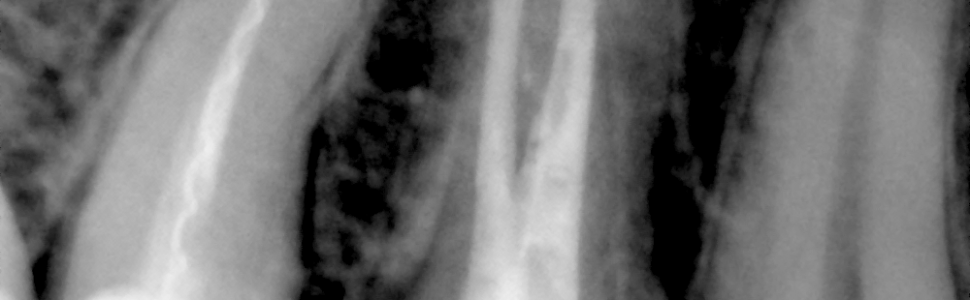

Mikroskopowa ewakuacja licznych złamanych narzędzi w obrębie kanałów zębów 14 i 15 przy zastosowaniu różnych technik zabiegowych

Jednym z głównych powodów niepowodzenia leczenia kanałowego jest złamanie narzędzi endodontycznych. Wśród najczęstszych przyczyn złamania narzędzi wymienia się niewłaściwą technikę pracy lekarza, skomplikowaną anatomię systemów kanałowych, niedokładną diagnostykę przedzabiegową, nieprawidłowe wykonanie dostępu endodontycznego oraz wady fabryczne narzędzi. Celem pracy było przedstawienie przypadku klinicznego ewakuacji mnogich złamanych narzędzi ze skomplikowanych anatomicznie systemów kanałowych zębów 14 i 15 przy użyciu różnych technik zabiegowych, wraz z uzasadnieniem wyboru danej techniki w konkretnej sytuacji klinicznej.

One of the most common reasons for the root canal treatment failure is iatrogenic fracture of endodontic files. Among the most common causes of a tool fracture the improper technique of the doctor’s work , complicated anatomy of root canal systems, inaccurate pre-treatment diagnosis , incorrect performance of endodontic access and manufacturing defects of files are mentioned. The aim of this report was to present a clinical case of evacuation of multiple broken tools within anatomically complex root canal systems of upper right premolars using various techniques, as well as their usage justification in a specific clinical situation.

Film 1. Lokalizacja otworów fizjologicznych na bocznych powierzchniach korzeni w obu zębach.

Film 2. Kanał typu „S” w zębie 15 i dowierzchołkowa pozycja złamanego narzędzia względem krzywizny kanału.

Film 3. Kłopotliwa ocena liczby złamanych narzędzi.